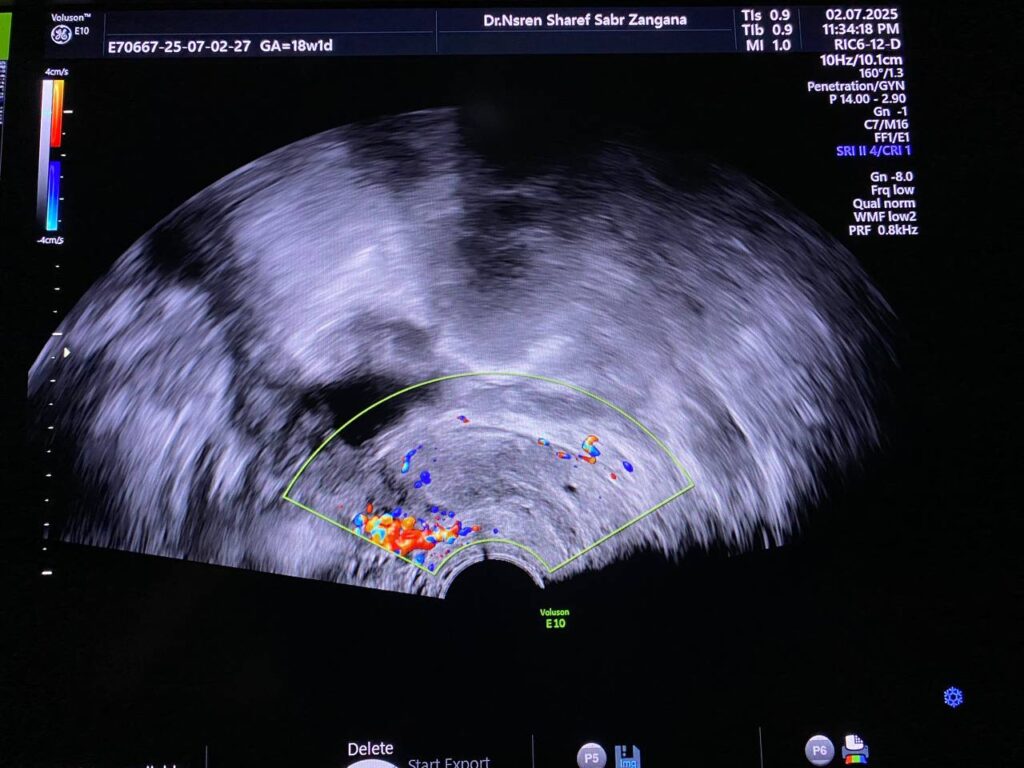

Bulky size, R/V uterus, endometrial lining thickness 13mm, with presence of isoechoic mass 36x12mm , within the cavity and nearly at level of interval os , incomplete abortion ? submucosal fibroid ? please for further study ill-defined endo-myometrial junctional zone, hypertrophy & asymmetry of the junctional myometrial layer, with presence few small cystic within the junctional layer, picture mostly of adenomyosis changes